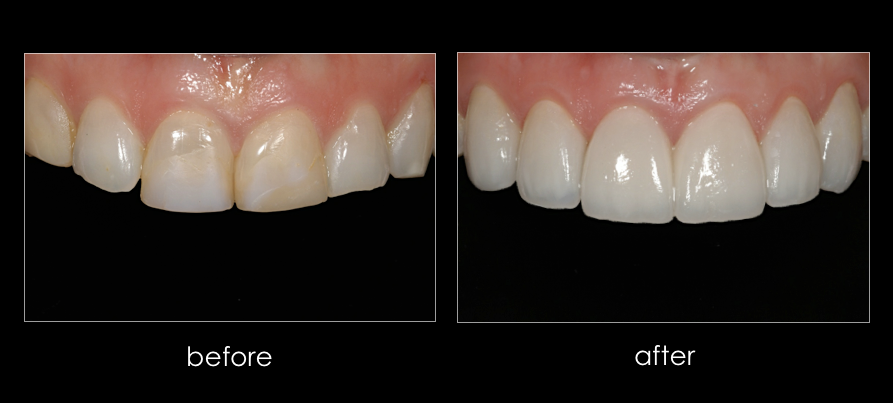

CASE 1. Female college lacrosse player from Gladwyne, with chipped and discolored front teeth resulting from repeated sports related trauma. The patient traveled from Virginia for treatment.